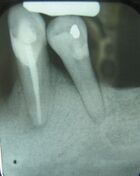

There are many types of investigations in diagnosis of oral and maxillofacial diseases, including screening tests, imaging (radiographs, CBCT, CT, MRI, ultrasound) and histopathology (biopsy).[5]